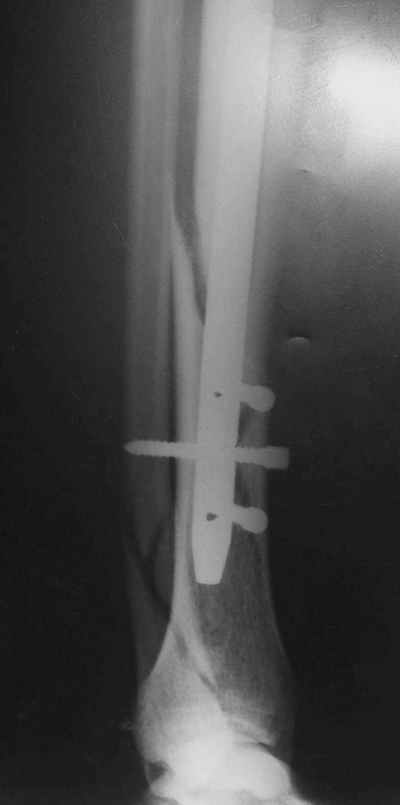

Не удается отправить первичные снимки. А что скажите по имеющимся?!

Выполненный остосинтез нестабилен. Штифт надо заменить по "размеру" на солидный, дистльно три запирающих винта. Успехов!

Перелом спиральный, то есть низкоэнергетический, так что со сращением дело обстоит уже неплохо, лишь бы "костоеда" не развилась. Отломки выглядят уже стабилизированными костной мозолью, так что довводить винты, наверно, уже незачем. Разве что при клинической оценке подвижность еще есть - тогда можно для стабилизации наложить простейший аппарат, не опасаясь контакта его элементов с гвоздем, поскольку места в дистальном метафизе оставлено более чем достаточно.

С Александром согласен, нет необходимости делать дополнительные усилия для сращения, не большая компрессия аппаратом из двух колец и полная нагрузка доделает работу.